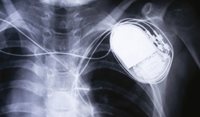

Cardiac rhythm management devices

01/05/2018

In the post-implant period, patients with cardiac rhythm management devices can expect to lead normal, active lives.